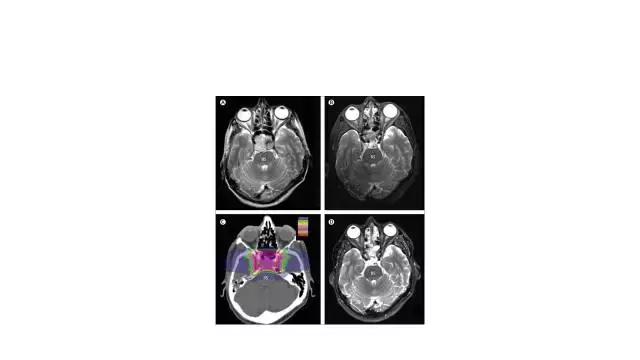

国际知名放疗专家、法国居里研究所Pierre Bey教授出席会议并在会上做学术报告《颅底肿瘤的质子放疗》,介绍了斜坡脊索瘤等颅内肿瘤质子临床应用的最新前沿进展。

以下 是Pierre Bey 教授的演讲PPT全文:(PPT由主办方和Pierre Bey教授合作团队-广州医科大学附属肿瘤医院张秀萍教授团队提供并授权我们发布)